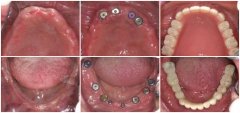

全口牙缺失修复前后